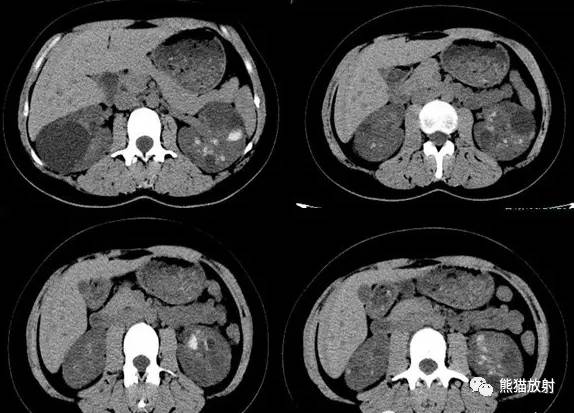

Additional history: The patient has a prior history of microhematuria and kidney stones. Review of the PACS for prior imaging reveals an intravenous pyelogram (IVP) from 2005. Scout and postcontrast exposures are shown below.

病史补充:患者之前患有镜下血尿及肾结石。回顾PACS中2005年的静脉尿路造影(IVP)图像,腹部平片及造影后图像图像所示。

IVP (2005): Preliminary scout images demonstrate a cluster of at least three radiopaque stones in the upper pole of the right kidney; the largest two stones in this cluster each measure 6 mm in diameter. In addition, there are probable clusters of smaller stones in the interpolar right kidney and right lower pole. Following the uneventful intravenous administration of 150 mL of nonionic contrast material, prompt nephrograms develop, which show the kidneys to be normal in size, shape, appearance, and internal architecture. There is diffuse bilateral tubular ectasia. Contrast is excreted promptly into otherwise normal-appearing pyelocalyceal systems. The calculi are no longer seen and likey reside in dilated tubules. The ureters are normal in course, caliber, and appearance. The urinary bladder has a mildly trabeculated appearance. There are two small urinary bladder diverticula: one of the bladder dome and one arising from the left lateral bladder wall. No filling defects are seen.

IVP:预扫定位像可见右肾上极至少3个阳性结石,簇状分布,最大的两个直径约6mm。另右肾中部及下极可见成簇的小结石。静脉注射非离子型对比剂150ml,立即摄片,可见肾脏大小、形态、表现及内部结构正常,可见弥漫性双侧肾小管扩张,造影剂进入正常的肾盂肾盏系统。钙化并未显示,可能在扩张的肾小管内。输尿管走行、直径及表现正常,膀胱轻度小梁形成,可见两个小膀胱憩室,一个位于膀胱顶壁,一个位于左侧壁;未见充盈缺损。

女性患者,24岁,体检发现。